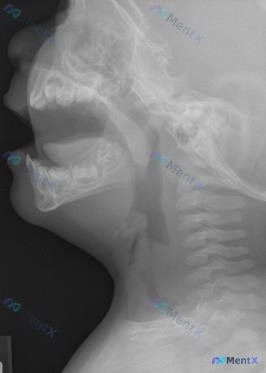

最近看到一份挺有警示意义的病例资料:9个月大的婴儿因为吞咽困难来就诊,拍了颈侧位X光片。我整理一下整个分析思路,里面有个很容易踩的坑。 先看病例核心信息 - 年龄:9个月婴儿 - 主诉:吞咽困难 - 影像:颈侧位X光片(原始报告描述了“颈椎变直”、“替牙期混合牙列”、“上颌前突下颌后缩”) ---...